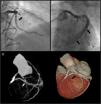

A 64-year-old Caucasian male with a history of coronary artery bypass grafting (CABG) [internal mammary artery (IMA) graft to the left anterior descending artery (LAD) and saphenous vein graft to right posterior descending artery (PDA)], presented with stable angina with a positive treadmill exercise test. Coronary angiography (CAG) documented occlusion of both middle LAD and IMA grafts (Figure 1, panel A); no significant lesions were found in the circumflex artery or the saphenous vein graft. The CAG performed prior to surgery is shown in Figure 2.

CT angiography showed a fistula from the middle segment of the LAD to the coronary sinus (Figure 1, panel C). Excluding the fistula by implanting a covered stent was then considered. However, when performing the initial CAG, complete stent restenosis had occurred, resulting in both LAD and fistula occlusion (Figure 3). A silent infarction had probably occurred. A new ischemia test was performed, documenting necrosis without viability. A conservative approach was therefore chosen.